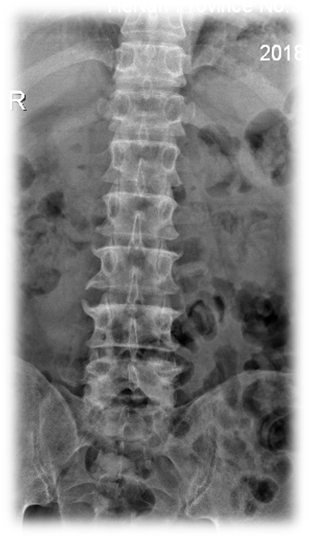

术前 图片1